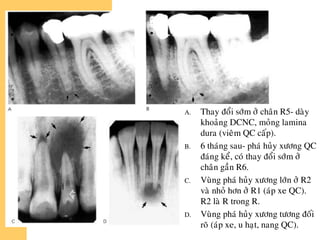

A. Thay ñoåi sôùm ôû chaân R5- daøy

khoaûng DCNC, moûng lamina

dura (vieâm QC caáp).

B. 6 thaùng sau- phaù huûy xöông QC

ñaùng keå, coù thay ñoåi sôùm ôû

chaân gaàn R6.

C. Vuøng phaù huûy xöông lôùn ôû R2

vaø nhoû hôn ôû R1 (aùp xe QC).

R2 laø R trong R.

D. Vuøng phaù huûy xöông töông ñoái

roõ (aùp xe, u haït, nang QC).